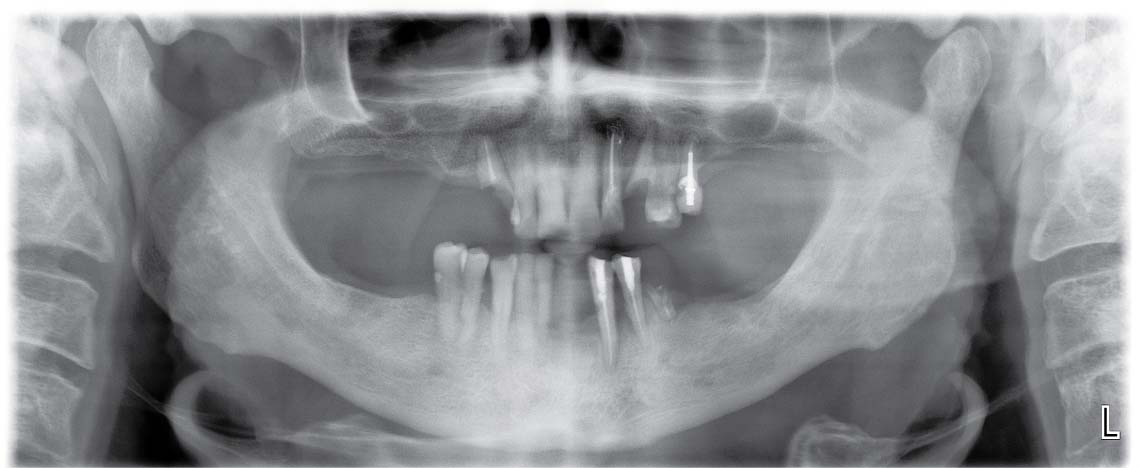

Случай 1: Лечение с импланти